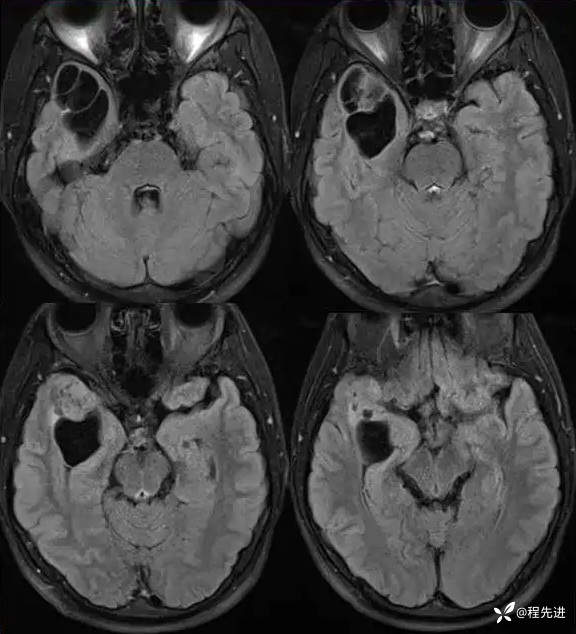

FLAIR: